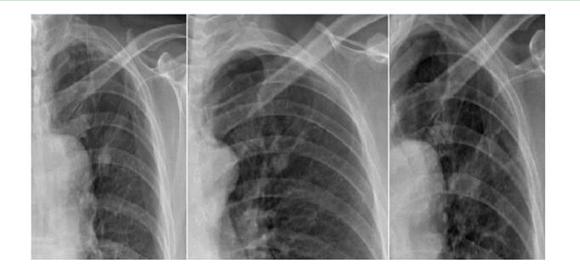

案例一:

第一年 第二年 第三年

案例解析:

在該案例中,病患在單一胸片檢查中,診斷出左上肺高密度結(jié)節(jié)影,前兩次在胸片攝影檢查得出的診斷結(jié)果并無大礙。相隔一年再去復(fù)查被誤診為“結(jié)核硬結(jié)灶”,并針對(duì)此而治療。但是,到了第三年之后,再次診斷發(fā)現(xiàn)結(jié)節(jié)影明顯增大,后才被確診為是肺癌,但為時(shí)已晚;如使用具備可視化點(diǎn)片功能的DR設(shè)備,胸片與胸透無縫結(jié)合,在透視下對(duì)“高密度結(jié)節(jié)影”全方位、多角度的高清點(diǎn)片獲取更多的確診信息,進(jìn)一步病理分析,第一時(shí)間得出確診結(jié)果,做到早發(fā)現(xiàn)、早治療,結(jié)果將會(huì)截然不同。